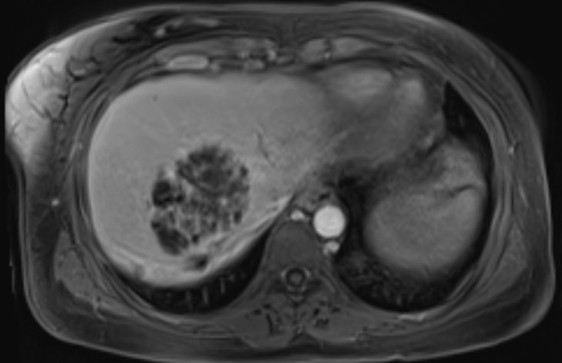

•Axial and coronal T2WI (HASTE sequences): An ~9cm hepatic mass with heterogenous, but predominately hyperintense signal, on T2WI. Associated intrahepatic biliary duct dilation with multiple curvilinear hypointense striations/filling defects.

Axial diffusion weighted imaging: mass and filling defects demonstrate hyperintense signal on high B value diffusion imaging •MRCP and axial T2 fat saturation: diffuse intrahepatic biliary duct dilation; axial T2 fat saturation images confirm HASTE findings.

•Pre and post-contrast T1 fat saturation images: predominately T1 hypointense mass with areas of intrinsic enhancement. Answer: Intraductal papillary neoplasm of the bile duct (IPNB)